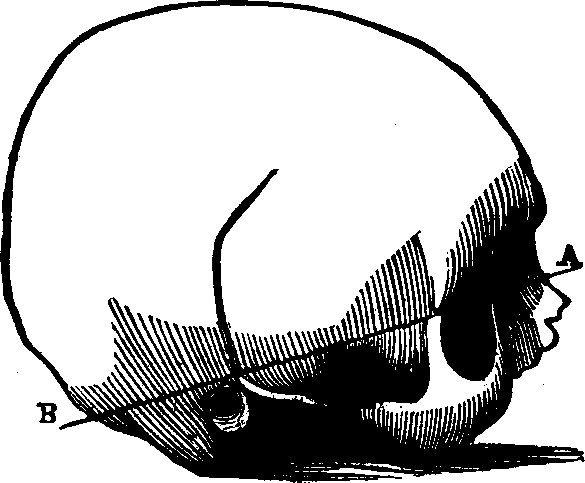

Fig. 10. The bones of the skull separated. 1. Frontal,

only half is seen. 2. Parietal. 3. Occipital, only half is

seen. 4. Temporal. 5. Nasal. 6. Malar. 7.

Superior maxillary (upper jaw). 8. Lachrymal. 9. Inferior

maxillary (lower jaw). Between 4 and 6 a part of the sphenoid

or wedge-shaped bone, is seen. Another bone assisting to form the skull,

but not here seen, is called the ethmoid (sieve-like, from being

full of holes), and is situated between the sockets of the eyes, forming

the roof of the nose.

The Bones of the Head are classed as follows: eight belonging to

the Cranium, and fourteen to the Face. The bones of the Cranium are the

occipital, two parietal, two temporal, frontal,

sphenoid, and ethmoid. Those composing the face are, the two

nasal, two superior maxillary, two lachrymal, two

malar two palate, two inferior turbinated, vomer, and

inferior maxillary. The cranial bones are composed of two dense

plates, between which there is, in most places a cancellated or cellular

tissue. The external [pg 23]plate is fibrous, the internal, compact and

vitreous. The skull is nearly oval in form, convex externally, the bone

being much thicker at the base than elsewhere, and it is, in every respect

admirably adapted to resist any injury to which it may be exposed, thus

affording ample protection to the brain substance which it envelops. The

internal surface of the cranium presents eminences and depressions for

lodging the convolutions of the brain, and numerous furrows for the

ramifications of the blood-vessels. The bones of the cranium are united to

one another by ragged edges called sutures, which are quite distinct

in the child but which in old age are nearly effaced. Some authorities

suppose that by this arrangement the cranium is less liable to be fractured

by blows; others think that the sutures allow the growth of these bones,

which takes place by a gradual osseous enlargement at the margins. The

bones of the Face are joined at the lower part and in front of the

cranium, and serve for the attachment of powerful muscles which assist in

the process of mastication. Although the soft parts of the face cover the

bony structure, yet they do not conceal its principal features, or

materially change its proportions. The form of the head and face presents

some remarkable dissimilarities in different races.